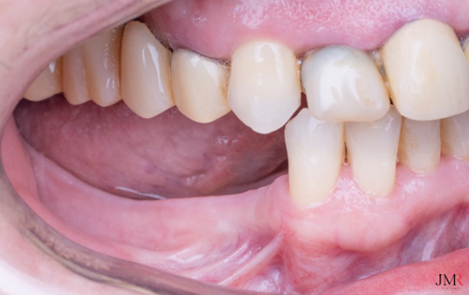

Figura 2.

Situación clínica inicial, donde se aprecia sobre todo, el componente horizontal de la atrofia y un espacio protésico reducido.